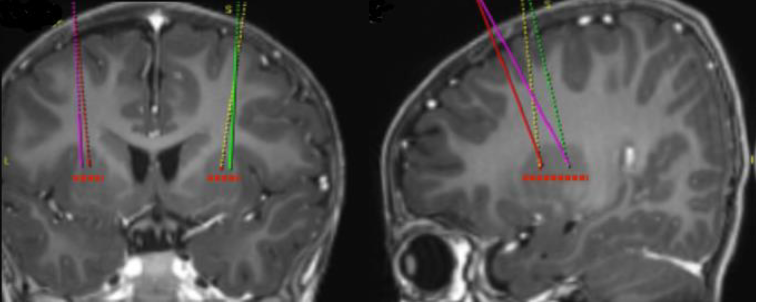

Målställena för infusionen definieras enligt standardiserad stereotaktisk neurokirurgisk praxis. Upstaza administreras som en bilateral infusion (2 infusioner per putamen) med en intrakraniell kanyl. De 4 slutliga målpunkterna för varje bana ska definieras som 2 mm dorsalt till (ovanför) de främre och bakre målpunkterna i det mitthorisontella planet (figur 1).

Figur 1 Fyra målpunkter för infusionsställen